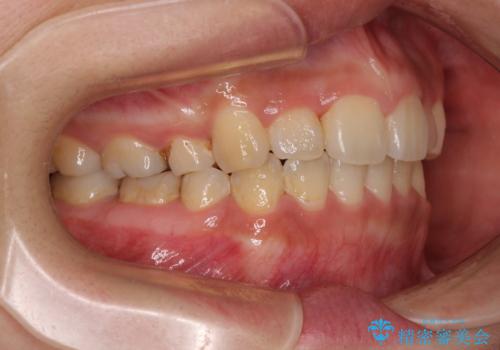

デコボコと膨らんだ口元 ハーフリンガルによる抜歯矯正とインプラント補綴治療

- 前歯のデコボコと上顎の前突感による口の閉じにくさを気にして来院された患者様です。

目立たない装置を希望されたので、上顎が裏側装置のハーフリンガルを選択し、上下左右の小臼歯(計4歯)を抜歯して矯正治療を行うこととしました。

デコボコの解消までは非常にスムーズでしたが、咬合力が強いためか、スペースを閉じるまでに長い期間を要しました。